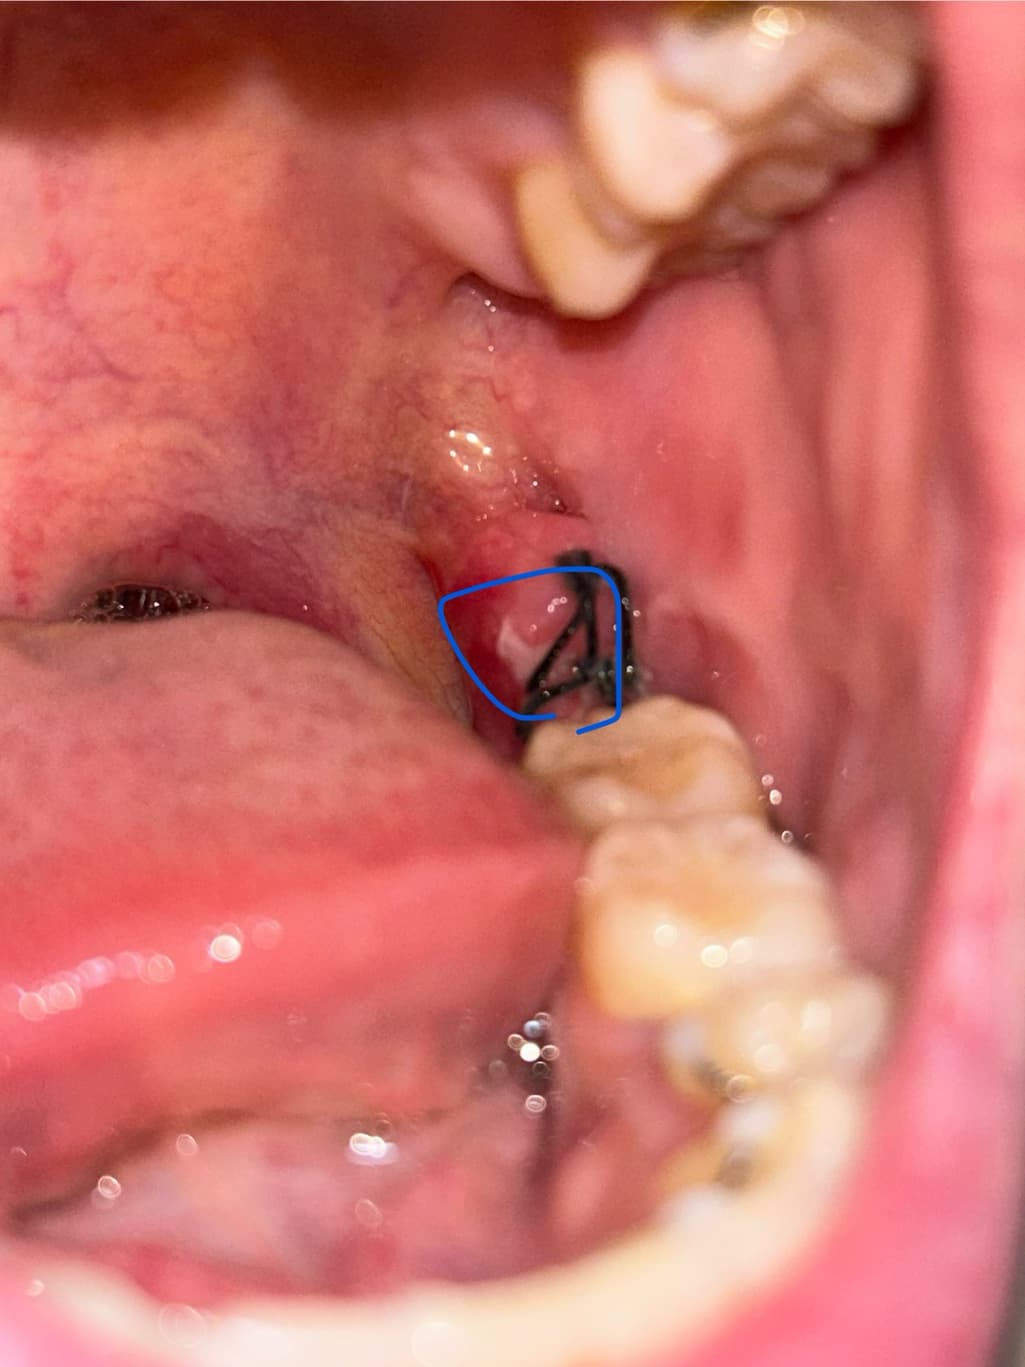

8월 9일 토요일에 왼쪽 아래 사랑니 발치후 현재 4일차입니다.

붓기는 나아지고 있는 것 같은데 잇몸에 하안게 퍼지는 것 같아요..

심각한 통증이나 그런건 없는데 염증인가요? 아님 치유과정 중 하나일까요..ㅠㅜ

사랑니를 발치 한 이후에 회복되는 과정에서 하얗게 막이 생기는 것은 정상적인 반응입니다.

사랑니를 발치하고 나면 발치한 부위가 아물면서 하얀색 가피 등이 형성될 수 있습니다. 이런 가피는 크게 문제가 되거나 하진 않기 때문에 걱정하지 않으셔도 되며 억지로 제거하려고 하지 않는 것이 좋습니다.

사진상으로 보면 발치한곳이 잘 아물고 잇는거 같습니다. 크게 걱정하실필요는 없을것같습니다.